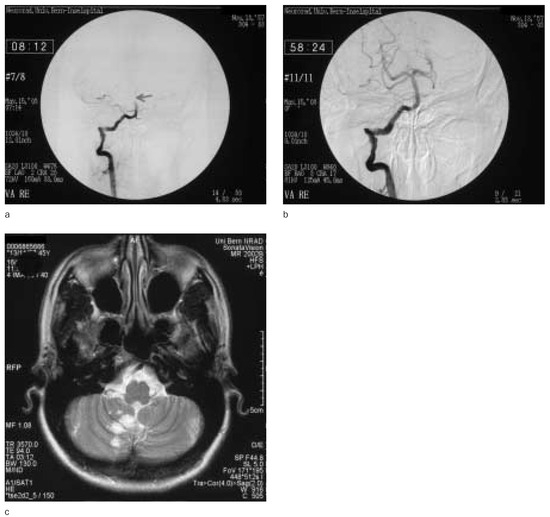

Endovascular treatment of cerebral arteriovenous malformations with emphasis on the curative role of embolisation

Cerebral arteriovenous malformations are complex and only partially understood vascular lesions of the central nervous system with a natural history characterised by significant morbidity and mortality mainly due to an increased haemorrhagic risk. Microneurosurgical removal, radiosurgical obliteration and neuroendovascular embolisation are the principal [...] Read more.

Cerebral arteriovenous malformations are complex and only partially understood vascular lesions of the central nervous system with a natural history characterised by significant morbidity and mortality mainly due to an increased haemorrhagic risk. Microneurosurgical removal, radiosurgical obliteration and neuroendovascular embolisation are the principal therapeutic modalities applied individually or in various combinations according to varying selection criteria for the treatment of cerebral arteriovenous malformations. In this context embolisation plays a central role either as a complementary or as the sole treatment technique. This report summarises the evolutive 18 years of continuous experience of the senior author with the neuroradiological evaluation and endovascular treatment of 644 patients with a cerebral arteriovenous malformation. Special emphasis is given to the underlying concepts and specific endovascular techniques developed for the complete, i.e. curative embolisation of cerebral arteriovenous malformations. Precise angiographic analysis of the vascular composition and intrinsic angioarchitecture of the nidus of the arteriovenous malformation by superselective microcatheterisation is required to identify the types of feeding arteries and patterns of their supply, the number and vascular connections of nidal compartments, the types of arteriovenous shunts, the morphology of the vascular spaces composing the nidus and the number and exit patterns of draining veins. Complete angiographic investigation for recognition of secondarily induced phenomena of the cerebral vasculature, such as arterial and venous high-flow angiopathy and so-called perinidal angiogenesis is essential for a comprehensive evaluation and assessment of the associated haemorrhagic risk. Based on a precise topographic classification, detailed angioarchitectural analysis, application of superselective multimicrocatheterisation techniques along with a controlled intranidal injection of non-absorbable liquid embolic materials, nearly 40% of cerebral arteriovenous malformations can be completely and stably obliterated and therefore curatively treated by single session or multistaged embolisation with a morbidity of 1.3% and a mortality of 1.3%, which are lower than the known natural history of this disease. Full article